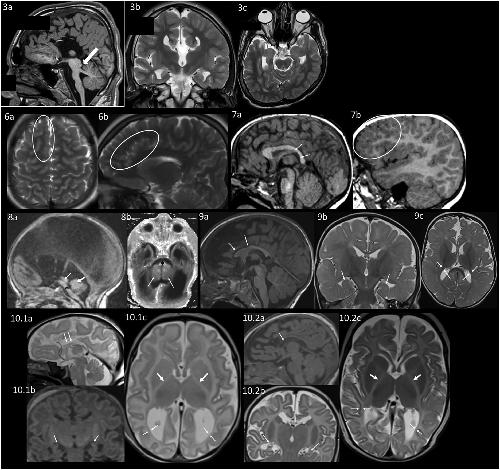

The genetic causes of global developmental delay (GDD) and intellectual disability (ID) are diverse and include variants in numerous ion channels and transporters. Loss-of-function variants in all five endosomal/lysosomal members of the CLC family of Cl- channels and Cl-/H+ exchangers lead to pathology in mice, humans, or both. We have identified nine variants in CLCN3, the gene encoding CIC-3, in 11 individuals with GDD/ID and neurodevelopmental disorders of varying severity. In addition to a homozygous frameshift variant in two siblings, we identified eight different heterozygous de novo missense variants. All have GDD/ID, mood or behavioral disorders, and dysmorphic features; 9/11 have structural brain abnormalities; and 6/11 have seizures. The homozygous variants are predicted to cause loss of ClC-3 function, resulting in severe neurological disease similar to the phenotype observed in Clcn3-/- mice. Their MRIs show possible neurodegeneration with thin corpora callosa and decreased white matter volumes. Individuals with heterozygous variants had a range of neurodevelopmental anomalies including agenesis of the corpus callosum, pons hypoplasia, and increased gyral folding. To characterize the altered function of the exchanger, electrophysiological analyses were performed in Xenopus oocytes and mammalian cells. Two variants, p.Ile607Thr and p.Thr570Ile, had increased currents at negative cytoplasmic voltages and loss of inhibition by luminal acidic pH. In contrast, two other variants showed no significant difference in the current properties. Overall, our work establishes a role for CLCN3 in human neurodevelopment and shows that both homozygous loss of ClC-3 and heterozygous variants can lead to GDD/ID and neuroanatomical abnormalities.